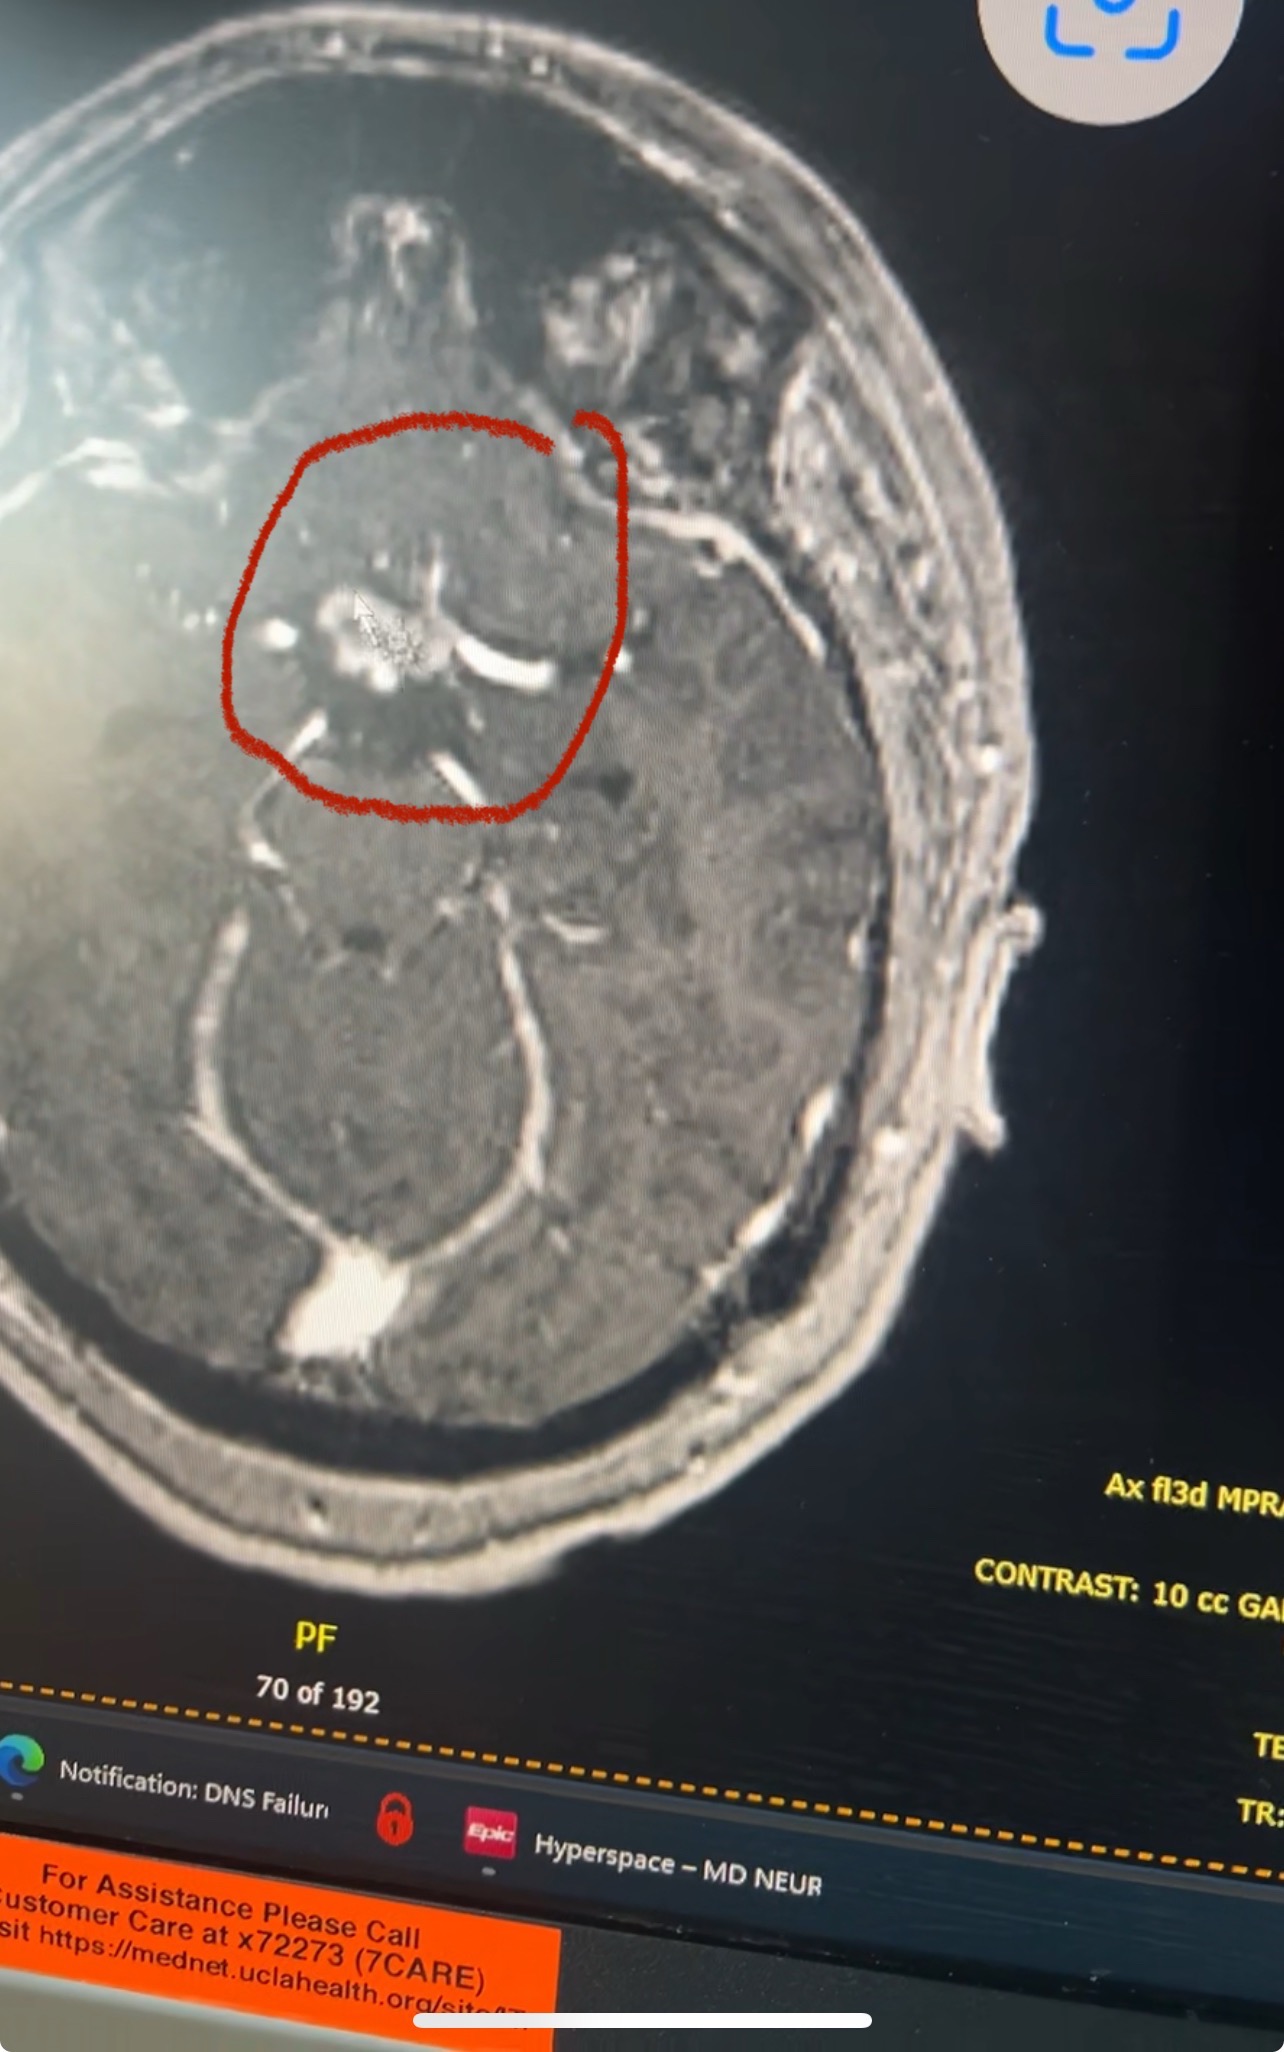

My son is only 24 years old and has been recently diagnosed with Germinoma Cancer of the brain. This diagnosis has turned our world upside down. He is my everything, and it’s heartbreaking to see him going through this. My son starts radiation this week. Please share and give what you can.